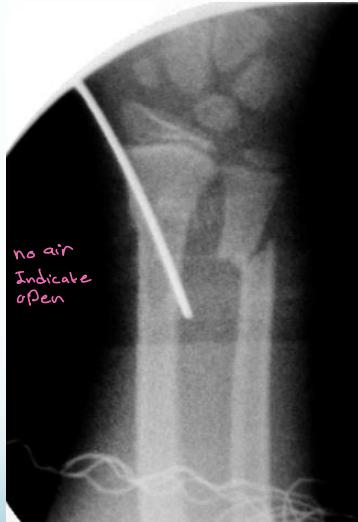

External Fixator

- Open (compound) fractures